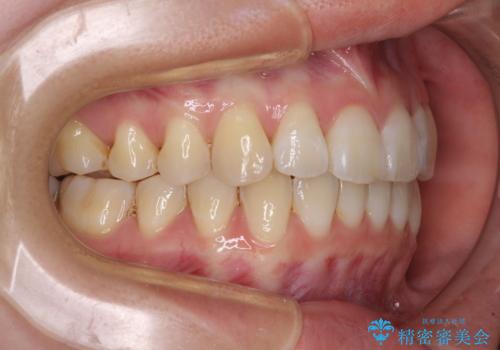

- 海外留学の予定があるが、学生のうちに歯列を整えたいとのことで来院された患者様です。

前歯にデコボコがあり、口元がやや突出した印象があったため、IPR(歯と歯の間を削る)と親知らずを抜歯した上での歯列全体の後方移動をメインに、インビザラインを用いて矯正治療を行うこととしました。

年に一度、夏休みの時期にしか帰国できないため、帰国のタイミングに合わせてマウスピース交換スケジュール治療計画としたため、3年半という期間を要しました。

留学先でもしっかりとマウスピースの装着を実践してくださったので、ご本人の満足のいく仕上がりとなりました。